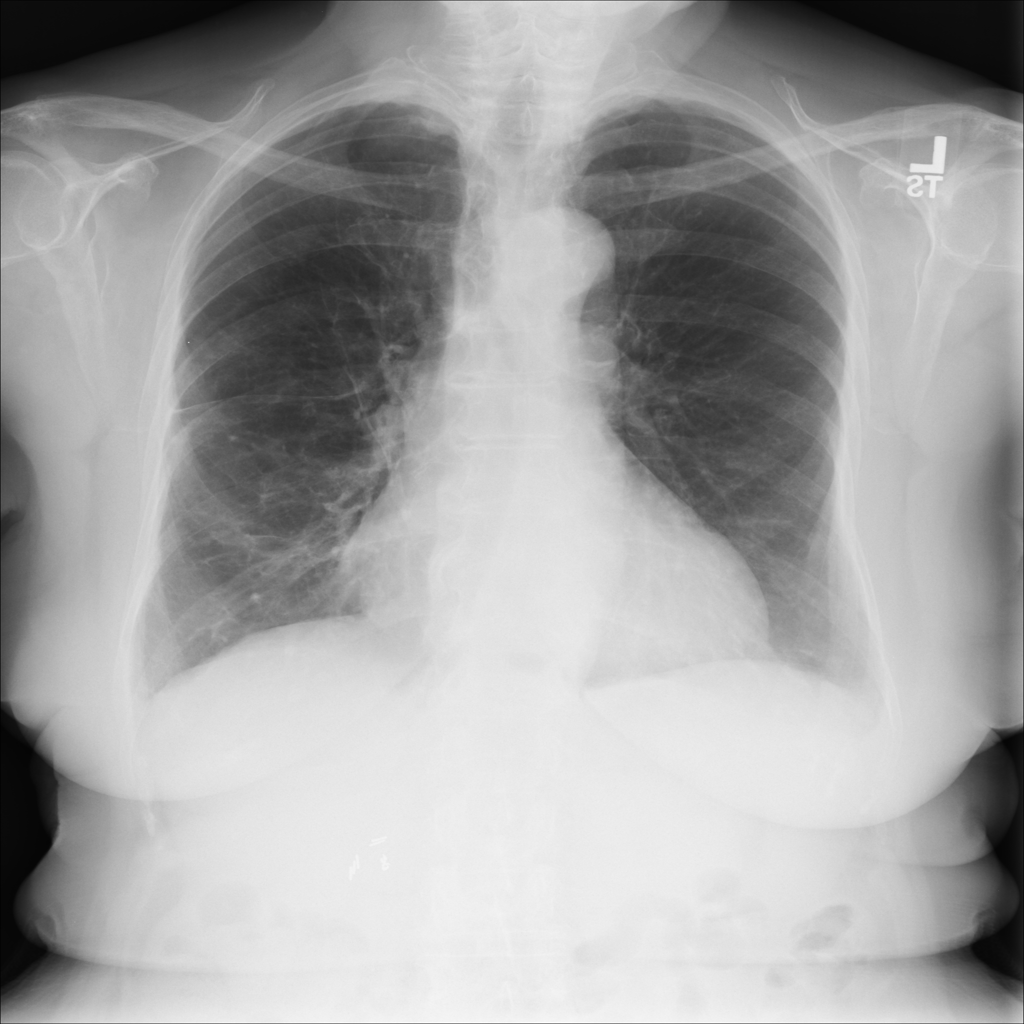

PAT-55FC · IMG-032Emphysema

PAT-55FC · IMG-032

AP